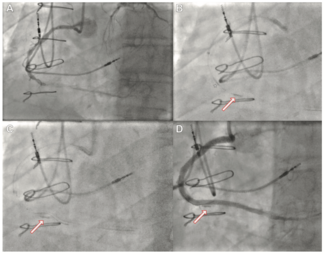

A 64-year-old female presented for closure of her left axillary access for intra-aortic balloon pump (IABP). We intended to close the access with standard balloon-assisted dry closure. A 7-Fr slender radial sheath was placed via left radial...